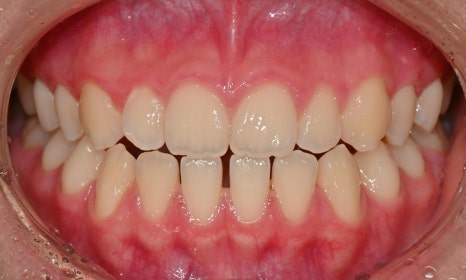

치료 전후 구내사진

1차 교정 후 앞니 반대교합이 재발하여 2차 교정을 진행한 케이스이며 성장기 막바지에 있긴 하지만 아직 성장이 끝난 것이 아니므로, 교정 치료가 마무리된 이후 다시 재발되지 않도록 유지 장치 관리를 잘 해주는 것이 중요할 것입니다.